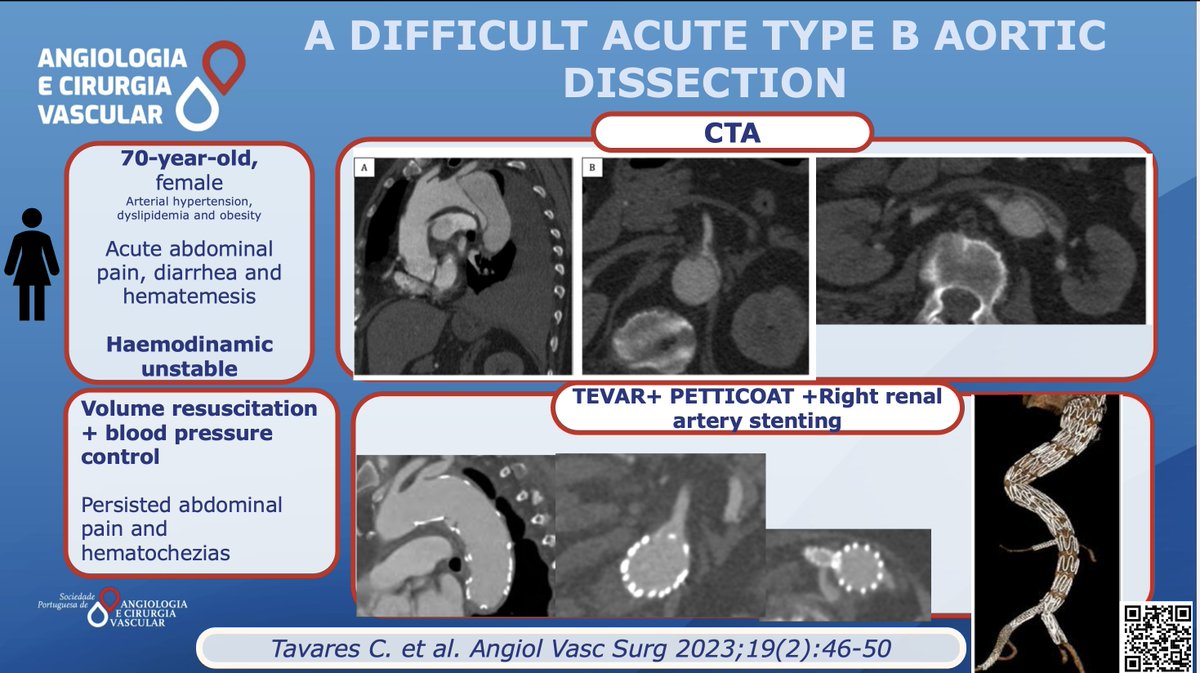

Here you can find the Endovascular solution chosen by Tavares C. et al acvjournal.com/index.php/acv/… #SPACV #Vascularsurgery #TypeBAcuteAorticDissection #TEVAR #PETICOAT European Vascular Surgeons in Training (EVST) ESVS Society for Vascular Surgery Vascular News